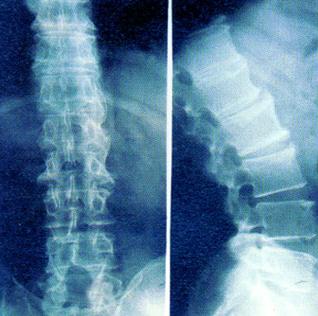

强直性脊柱炎能治好吗?